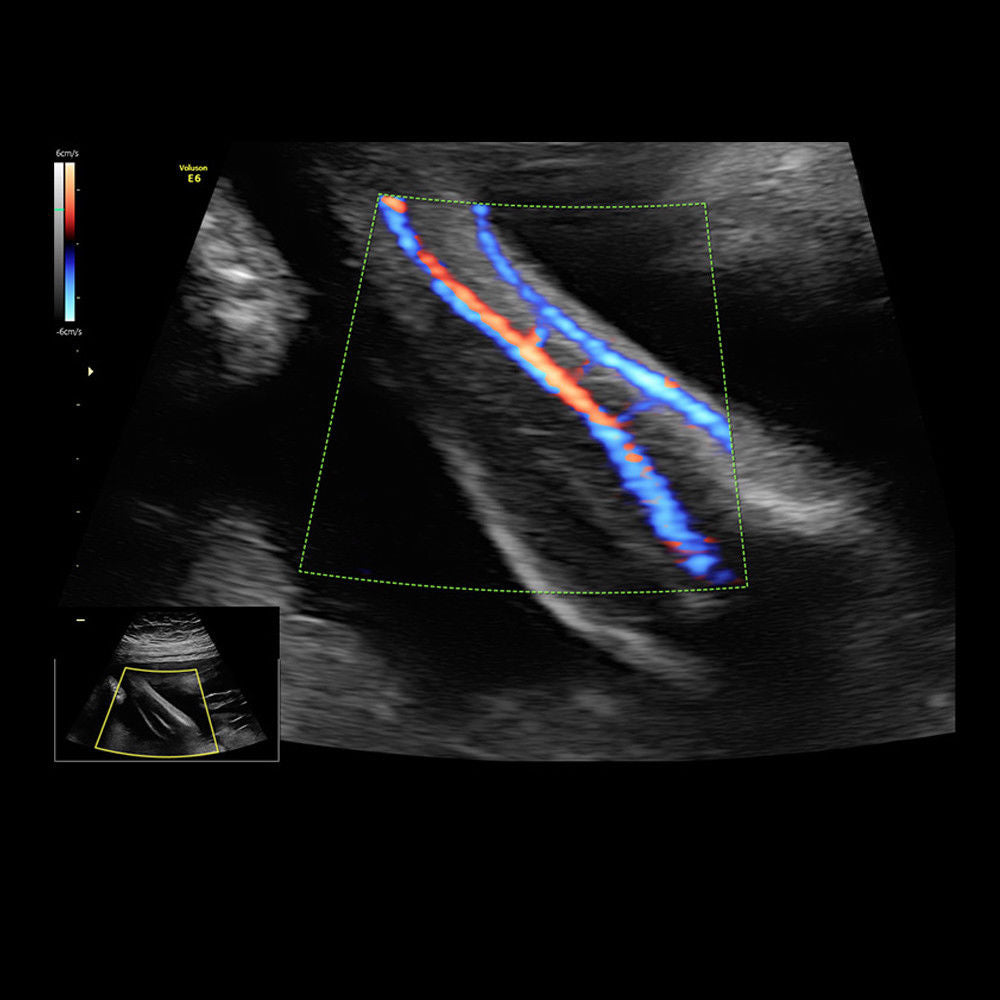

Brand: HD LIVE 4D

MPN: 4DHDLIVE-RAB6-D-SYSTEM-VOLUMETRIC-CONVEX